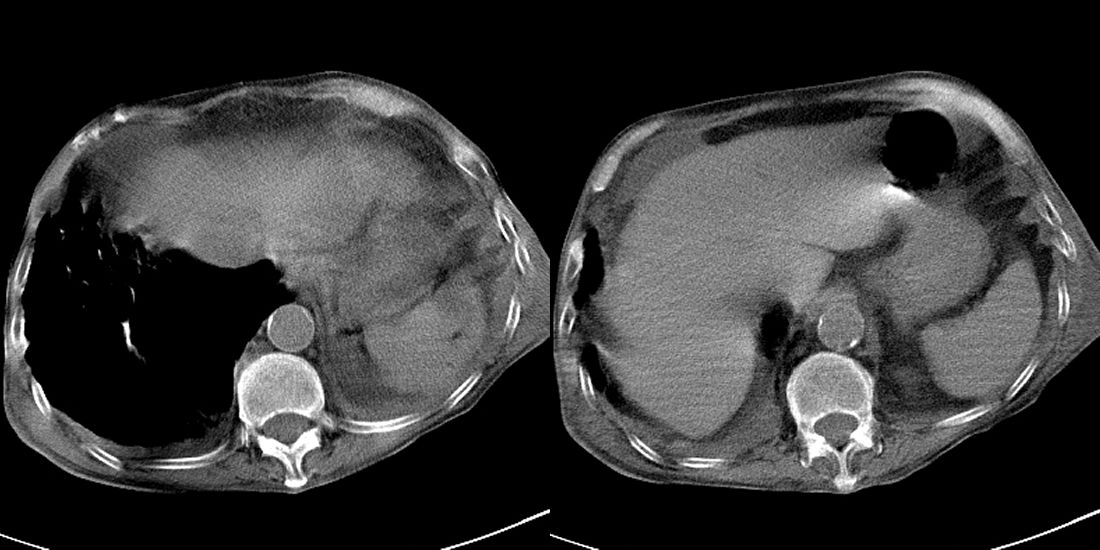

以下是引用liuyue在2008-11-30 6:01:00的发言:[br]双肺继发性肺结核;左侧包裹性积液;建议增强化或支气管镜检查除外左肺占位性病变.

以下是引用吴承学在2008-11-30 8:02:00的发言:[br]双肺继发性肺结核;左侧包裹性积液;建议增强化或支气管镜检查除外左肺占位性病变.[br]